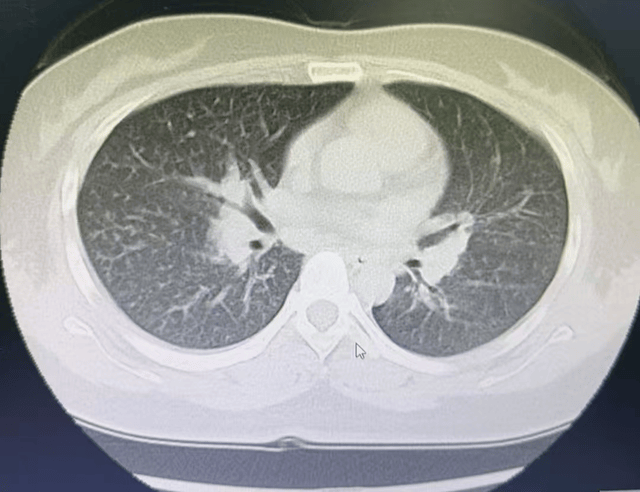

近日,江苏淮安一名35岁二胎宝妈,每日频繁使用84消毒液消毒,约一个月后,她患上十万分之一的急性嗜酸性粒细胞肺炎。

约一个月前张女士逐渐出现胸闷气喘、呼吸困难等症状。医生诊断其患上了“急性嗜酸性粒细胞肺炎”这种罕见病。

图片来源:淮安市第二人民医院